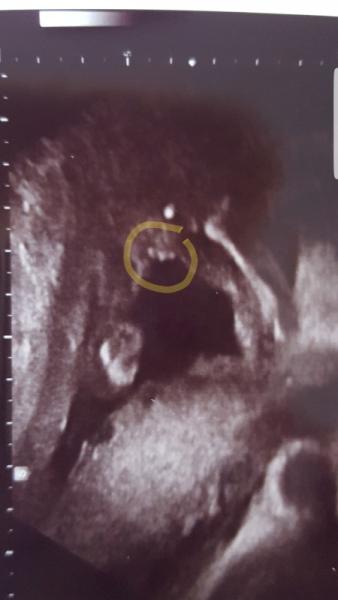

Huhu Was seht ihr als Geschlecht? Mein FA hat es uns gesagt jedoch wollte ich mal fragen was ihr seht;) LG Jessi 18+4

Bild zu Outing - Schwanger - wer noch? Rund um die Schwangerschaft

Ein Mädchen

Mädchen würd ich sagen :-)

Mädchen. Meine Jungs sahen anders aus.

Auf jeden Fall sieht das nach Mädchen aus. Einen Penis ist im US viel länger und dicker.

Ihr lagt alle richtig;) Freuen uns sehr auf unser Mädchen ♡